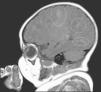

Presentamos el caso de una lactante de 51 días de edad nacida a término con gestación y parto sin incidencias, de padres sanos no consanguíneos que acudió a la unidad de urgencias de pediatría por crisis convulsivas continuas desde hacía tres días. A la exploración física destacaba la presencia de máculas hipopigmentadas ovales y lanceoladas de 3–11mm de diámetro en miembros y tronco (fig. 1). Llamaba la atención la presencia de poliosis en la mitad interna del párpado superior izquierdo y otra mácula hipopigmentada en el canto interno del ojo (fig. 2), que estaban presentes en el momento del nacimiento. Con la sospecha clínica de esclerosis tuberosa, se le practicó una RMN cerebral que mostró múltiples tuberomas corticales (fig. 3), y un electroencefalograma, en el que se detectaron focos irritativos. El resto de pruebas diagnósticas, incluido en el fondo de ojo, fueron normales. Se inició tratamiento con ácido valproico y vigabatrina, con buena tolerancia y control de los síntomas. El estudio de los padres fue negativo.